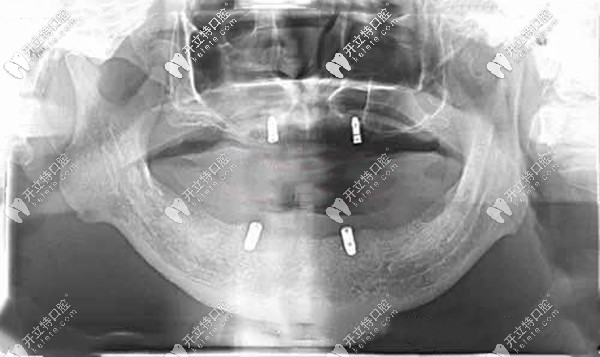

全口無牙頜種植覆蓋義齒后的CT片▼